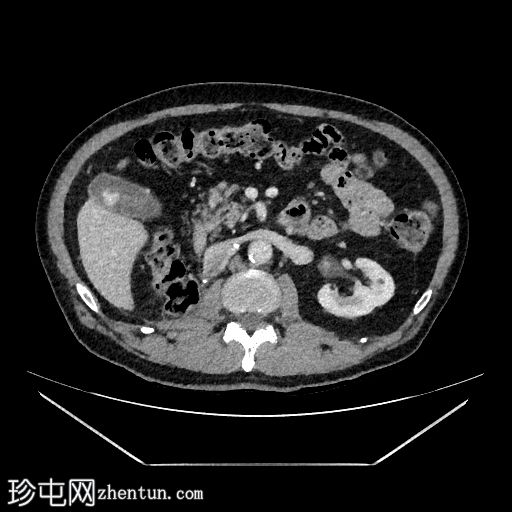

轴位增强扫描(C+)门静脉期

行CT检查以进行分期。已知肾细胞癌。已行右侧根治性肾切除术和左侧肾上腺切除术。胆囊内可见强化物质,提示胆囊底部血管受累。骨窗下胆囊内未见钙化灶。影像表现提示胆囊转移。